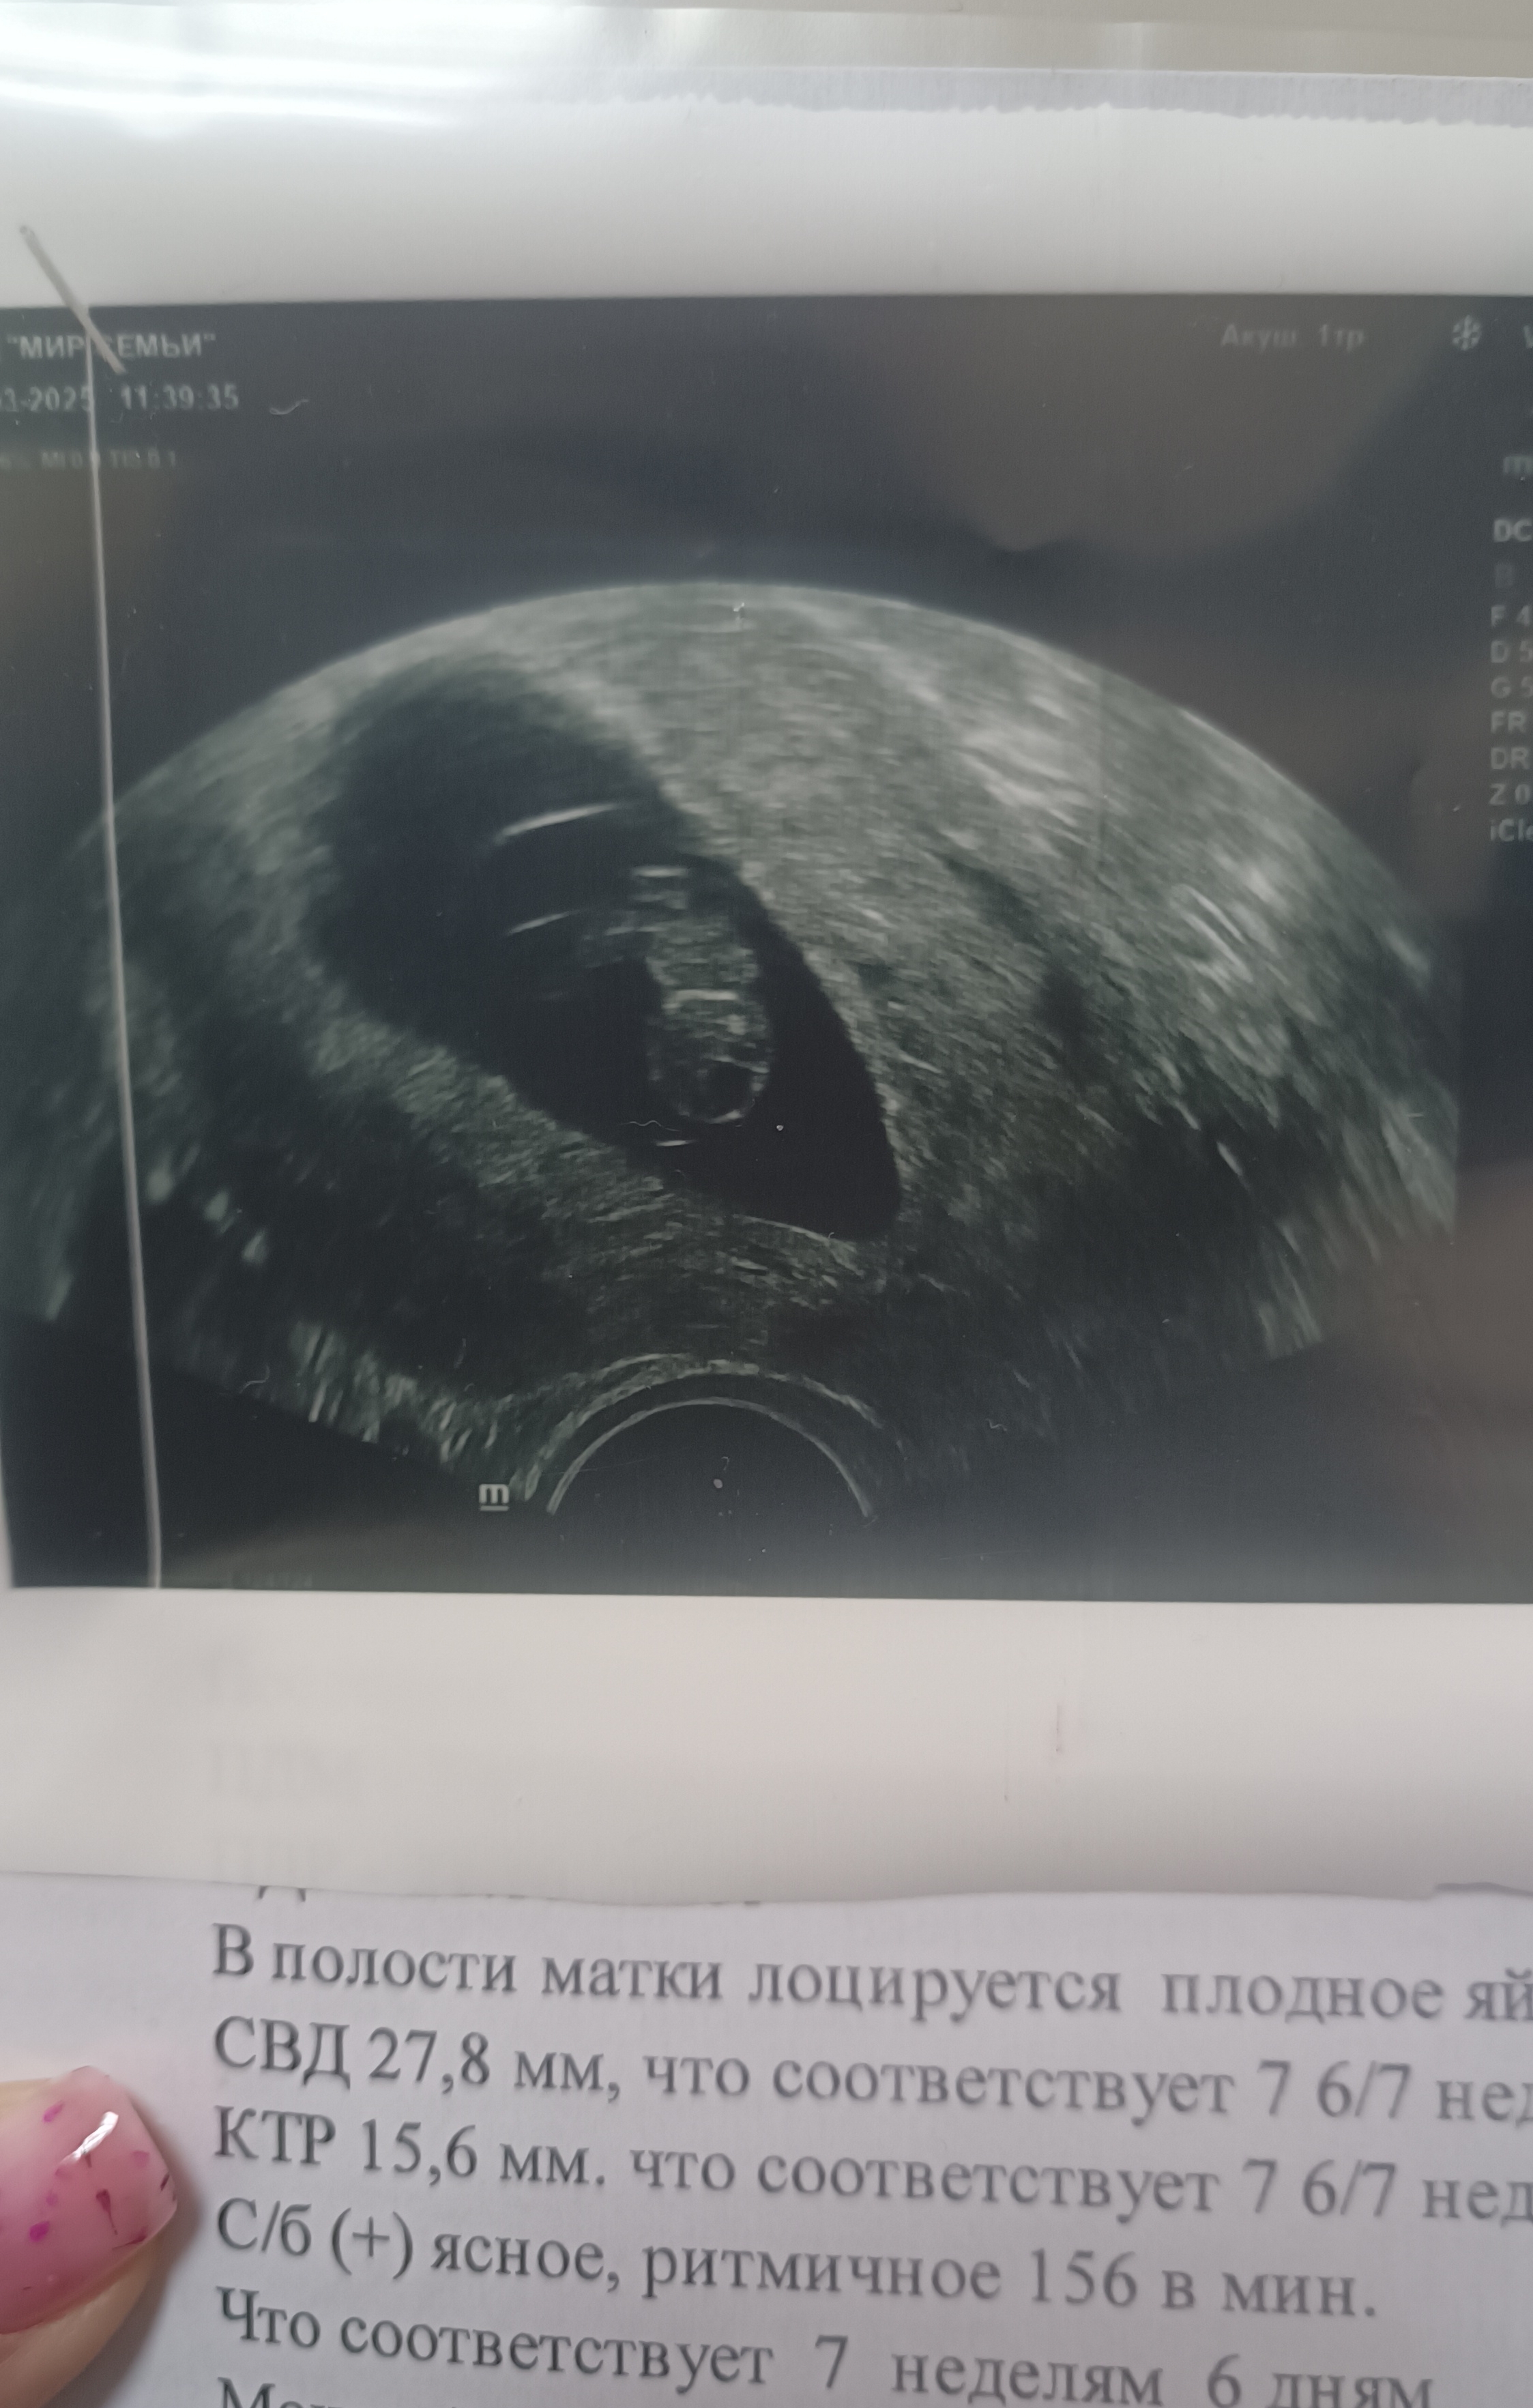

По сроку 7 недель 6 дней. Все соответствует сроку) Дали послушать сердечко. Проверили пульсацию пуповины. КТР 15,6 мм. СБ 156.